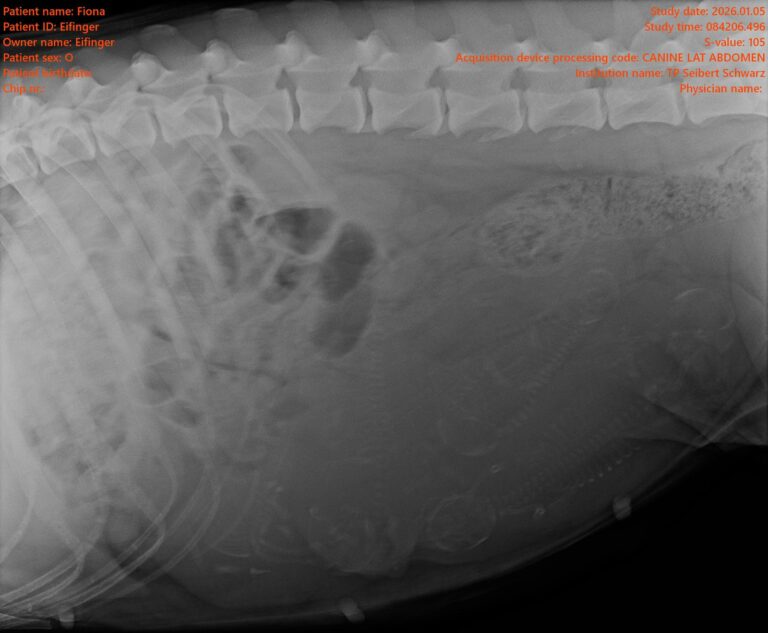

Es gibt erfreuliche Nachrichten – 6 Welpen werden erwartet!